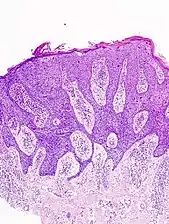

Histopathologically, the epidermis in cSCC in situ (Bowen's disease) will show hyperkeratosis and parakeratosis. There will also be marked acanthosis with elongation and thickening of the rete ridges. These changes will overly keratinocytic cells which are often highly atypical and may in fact have a more unusual appearance than invasive cSCC. The atypia spans the full thickness of the epidermis, with the keratinocytes demonstrating intense mitotic activity, pleomorphism, and greatly enlarged nuclei. They will also show a loss of maturity and polarity, giving the epidermis a disordered or "windblown" appearance.

Two types of multinucleated cells may be seen: the first will present as a multinucleated giant cell, and the second will appear as a dyskeratotic cell engulfed in the cytoplasm of a keratinocyte. Occasionally, cells of the upper epidermis will undergo vacuolization, demonstrating an abundant and strongly eosinophilic cytoplasm. There may be a mild to moderate lymphohistiocytic infiltrate detected in the upper dermis.[12]

Histopathology of squamous-cell carcinoma in situ (black arrow), compared to normal skin, showing marked atypia.

Squamous-cell carcinoma in situ, showing prominent dyskeratosis and aberrant mitoses at all levels of the epidermis, along with marked parakeratosis.[12]